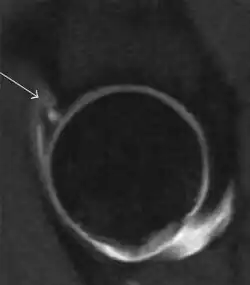

Most of the angles and measurements described in the plain radiograph section can be accurately reproduced on MRI. In addition, the superiority of MRI resolution with intra-articular contrast allows detection of labral and chondral abnormalities that may influence the choice of medical, percutaneous, or surgical management (Figure 9).[1]

Figure 9:

Sagittal T1 weighted image showing anterosuperior labral tear.[1] -

MR arthrography has proven superior in accuracy when compared to native MR imaging. It is considered the best technique to assess the labrum. Knowledge of the normal variable morphology of the labrum helps to differentiate tears from normal variants. A triangular shape is most commonly seen in 66% of asymptomatic volunteers, but round, flattened, and absent labra can also be found in asymptomatic populations. MR arthrography has demonstrated sensitivity over 90% and specificity close to 100% in detecting labral tears. Loose bodies are demonstrated as filling defects surrounded by the hyperintense gadolinium.[1]

Association between labral tears and chondral damage has been demonstrated. This underscores the interaction between cartilage and labrum damage in the progression of osteoarthritis. Chondral damage to the posteroinferior part of the acetabulum as a contrecoup lesion occurs in approximately one-third of pincer cases secondary to persistent abutment on the anterior part of the joint leading to a slight posteroinferior subluxation. This is considered a bad prognosis sign.[1]